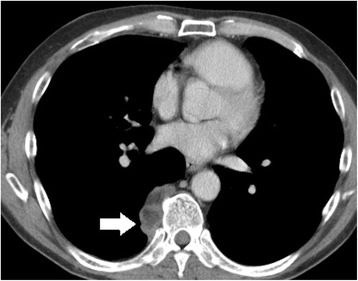

Fig. 1.

Chest CT at our hospital showed a tumor in the right posterior mediastinum (arrow). It measured 4.3 cm in diameter and was located beside the 9th thoracic vertebrae